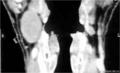

В диагностике боковой кисты шеи большое значение имеет КТ в режиме контрастирования, которая позволяет уточнить локализацию, топографические особенности ее расположения, размеры, плотность содержимого и состояние региональных лимфатических узлов.

На КТ шеи (слева) обозревается наличие инкапсулированной кисты, расположенная кпереди грудино-ключично-сосцевидной мышцы, на уровне подъязычной кости и щитовидного хряща. Форма кисты веретенообразная, размеры 3 см в переднезаднем и 2,5 см в поперечном измерение: вертикальный размер не менее 5 см. Внутри она имеет однородное кистозно-жидкостное содержимое (серозный мукоид) плотностью до 26 ед Н. Сонные артерии и внутренняя яремная вена расположены позади и медиальнее кисты - непосредственно прилегают к ее внутренней поверхности .

На КТ справа по переднебоковой поверхности шеи кпереди от сосудисто-нервного пучка, медиальнее от грудино-ключично-сосцевидной мышцы обозревается плотная тканевая структура которая проецируется на уровне подъязычной кости и щитовидного хряща. Размеры 4х2,5 см. Сонные артерии и внутренняя яремная вена оттеснены медиально.